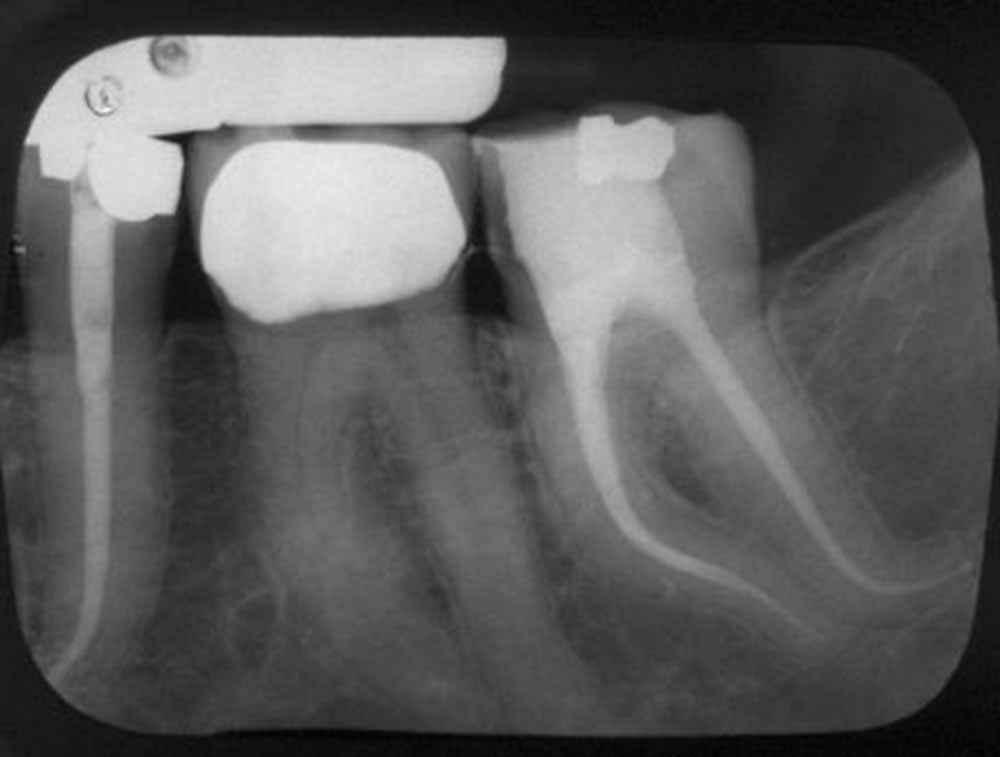

Endodonti (Kanal tedavileri,fiber post uygulamaları)